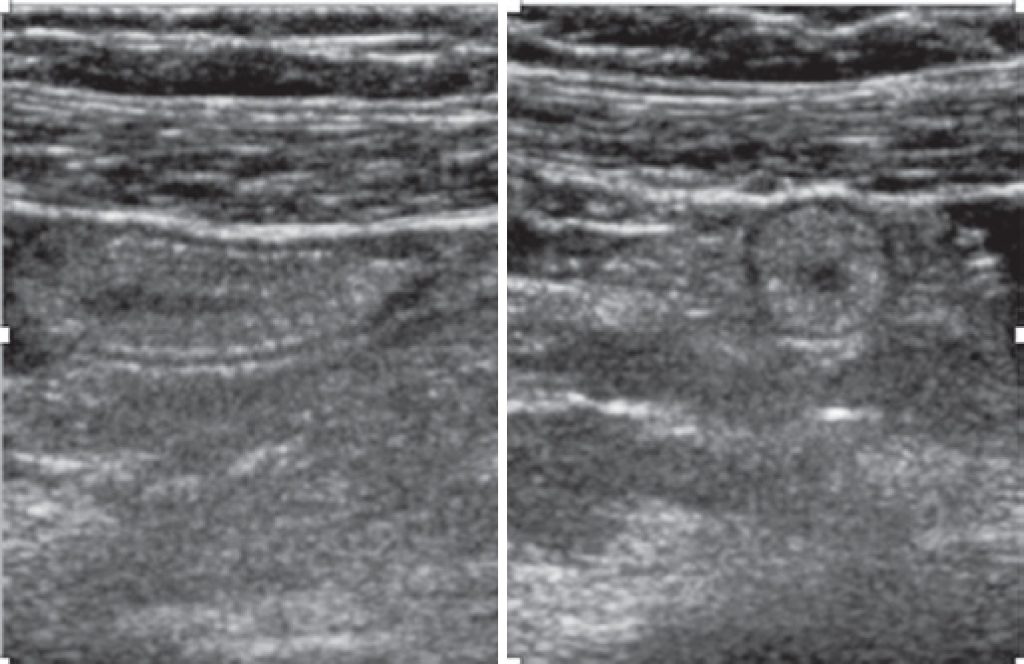

Figure 2. Caecal appendix with thicker wall identified in the ultrasonography

A 34-years-old pregnant woman admitted in the emergency unit complaining about worsening right iliac fossa pain for 2 days. Acute appendicitis was the suspected diagnosis. Laboratory exams were ordered and results were within normal limits for infectious and inflammatory aspects. Ultrasound scan revealed a pregnancy in course without alterations and a thickness of the appendix wall without inflammatory signs in the surrounding tissue. Because the suspicion of acute appendicitis remained, a magnetic resonance was done and confirmed the diagnosis of a cecal appendix lipomatosis.